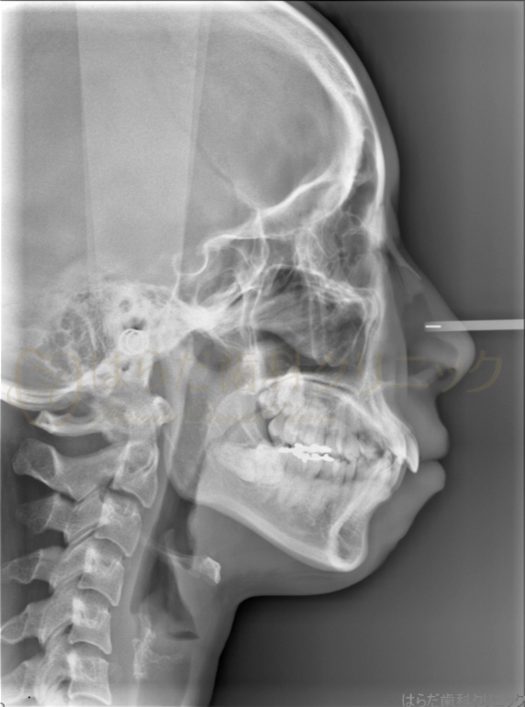

舌側矯正の症例紹介

Before

主訴

上下の歯並びが気になるけれども矯正器具が目立つのも気になる

治療内容

舌側矯正

スペースを確保するため上下左右4番目を抜歯いたしました。

その後、全体的に歯の裏にて矯正をいたしました。

今回使用した矯正装置はメタルブラケットになります。

治療費

総額:1,596,100円(税込)

矯正相談料:1,100円(税込)

矯正検査料:44,000円(税込)

矯正装置料:1,320,000円(税込)

抜歯料:22,000円(税込)(5,500円×4)

調整管理料:176,000円(税込)(5,500円×32)

保定装置料:33,000円(税込)

治療期間

約3年7か月

通院回数

35回

想定されたリスク

※以下の可能性がありました。

・歯が動くことに伴う痛み

・歯肉退縮、歯根吸収、矯正装置をつけることによるむし歯、歯周病のリスク

・しゃべりにくい、歯ブラシがしにくい

・治療期間が長くなる